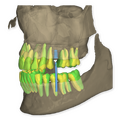

The DSD Interdisciplinary is a digital wax up of the upper and lower arches, designed considering a facially-driven, clinical and functional analysis of the patient.

It is our most comprehensive planning option, and includes all the 3D treatment simulations needed for each case, such as ortho, perio, implants, grafts and orthognathic surgery.

Our 3D simulations showcase various treatment suggestions, facilitating a deeper understanding of the required procedures. This leads to the creation of a broader treatment plan and enables a more efficient communication with your patients.